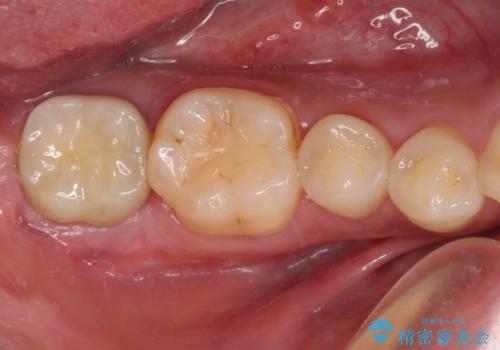

- 上顎4前歯に装着されているセラミッククラウンのうち、ひとつが欠けてしまったとのことで来院された患者様です。

土台となっている歯には問題がないため、周囲のセラミッククラウンと色調が合うように、オーダーメイドタイプのセラミッククラウンにて補綴治療を行うこととしました.

欠けてしまったセラミッククラウンはガラス系セラミッククラウンであったため、今回製作する歯は、強度の強いジルコニアセラミッククラウンとしました。

クラウンの種類は異なりますが、色調の適合したクラウンを装着することができました。